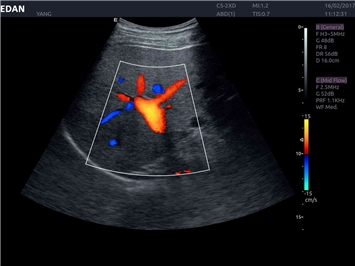

Трехмерная реконструкция ЦДК:

Да

Color 3D: